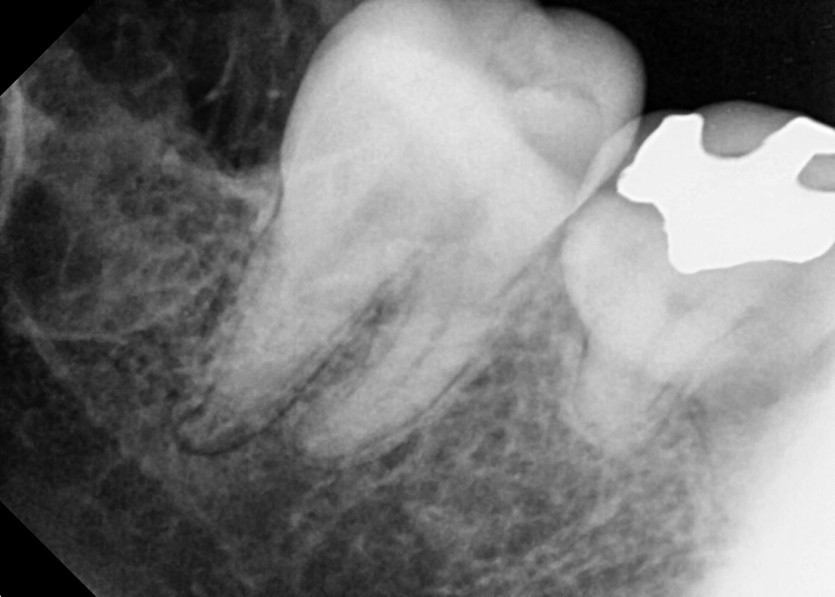

#48 사랑니 발치

구강 외과 전문의가 당일 발치했습니다.